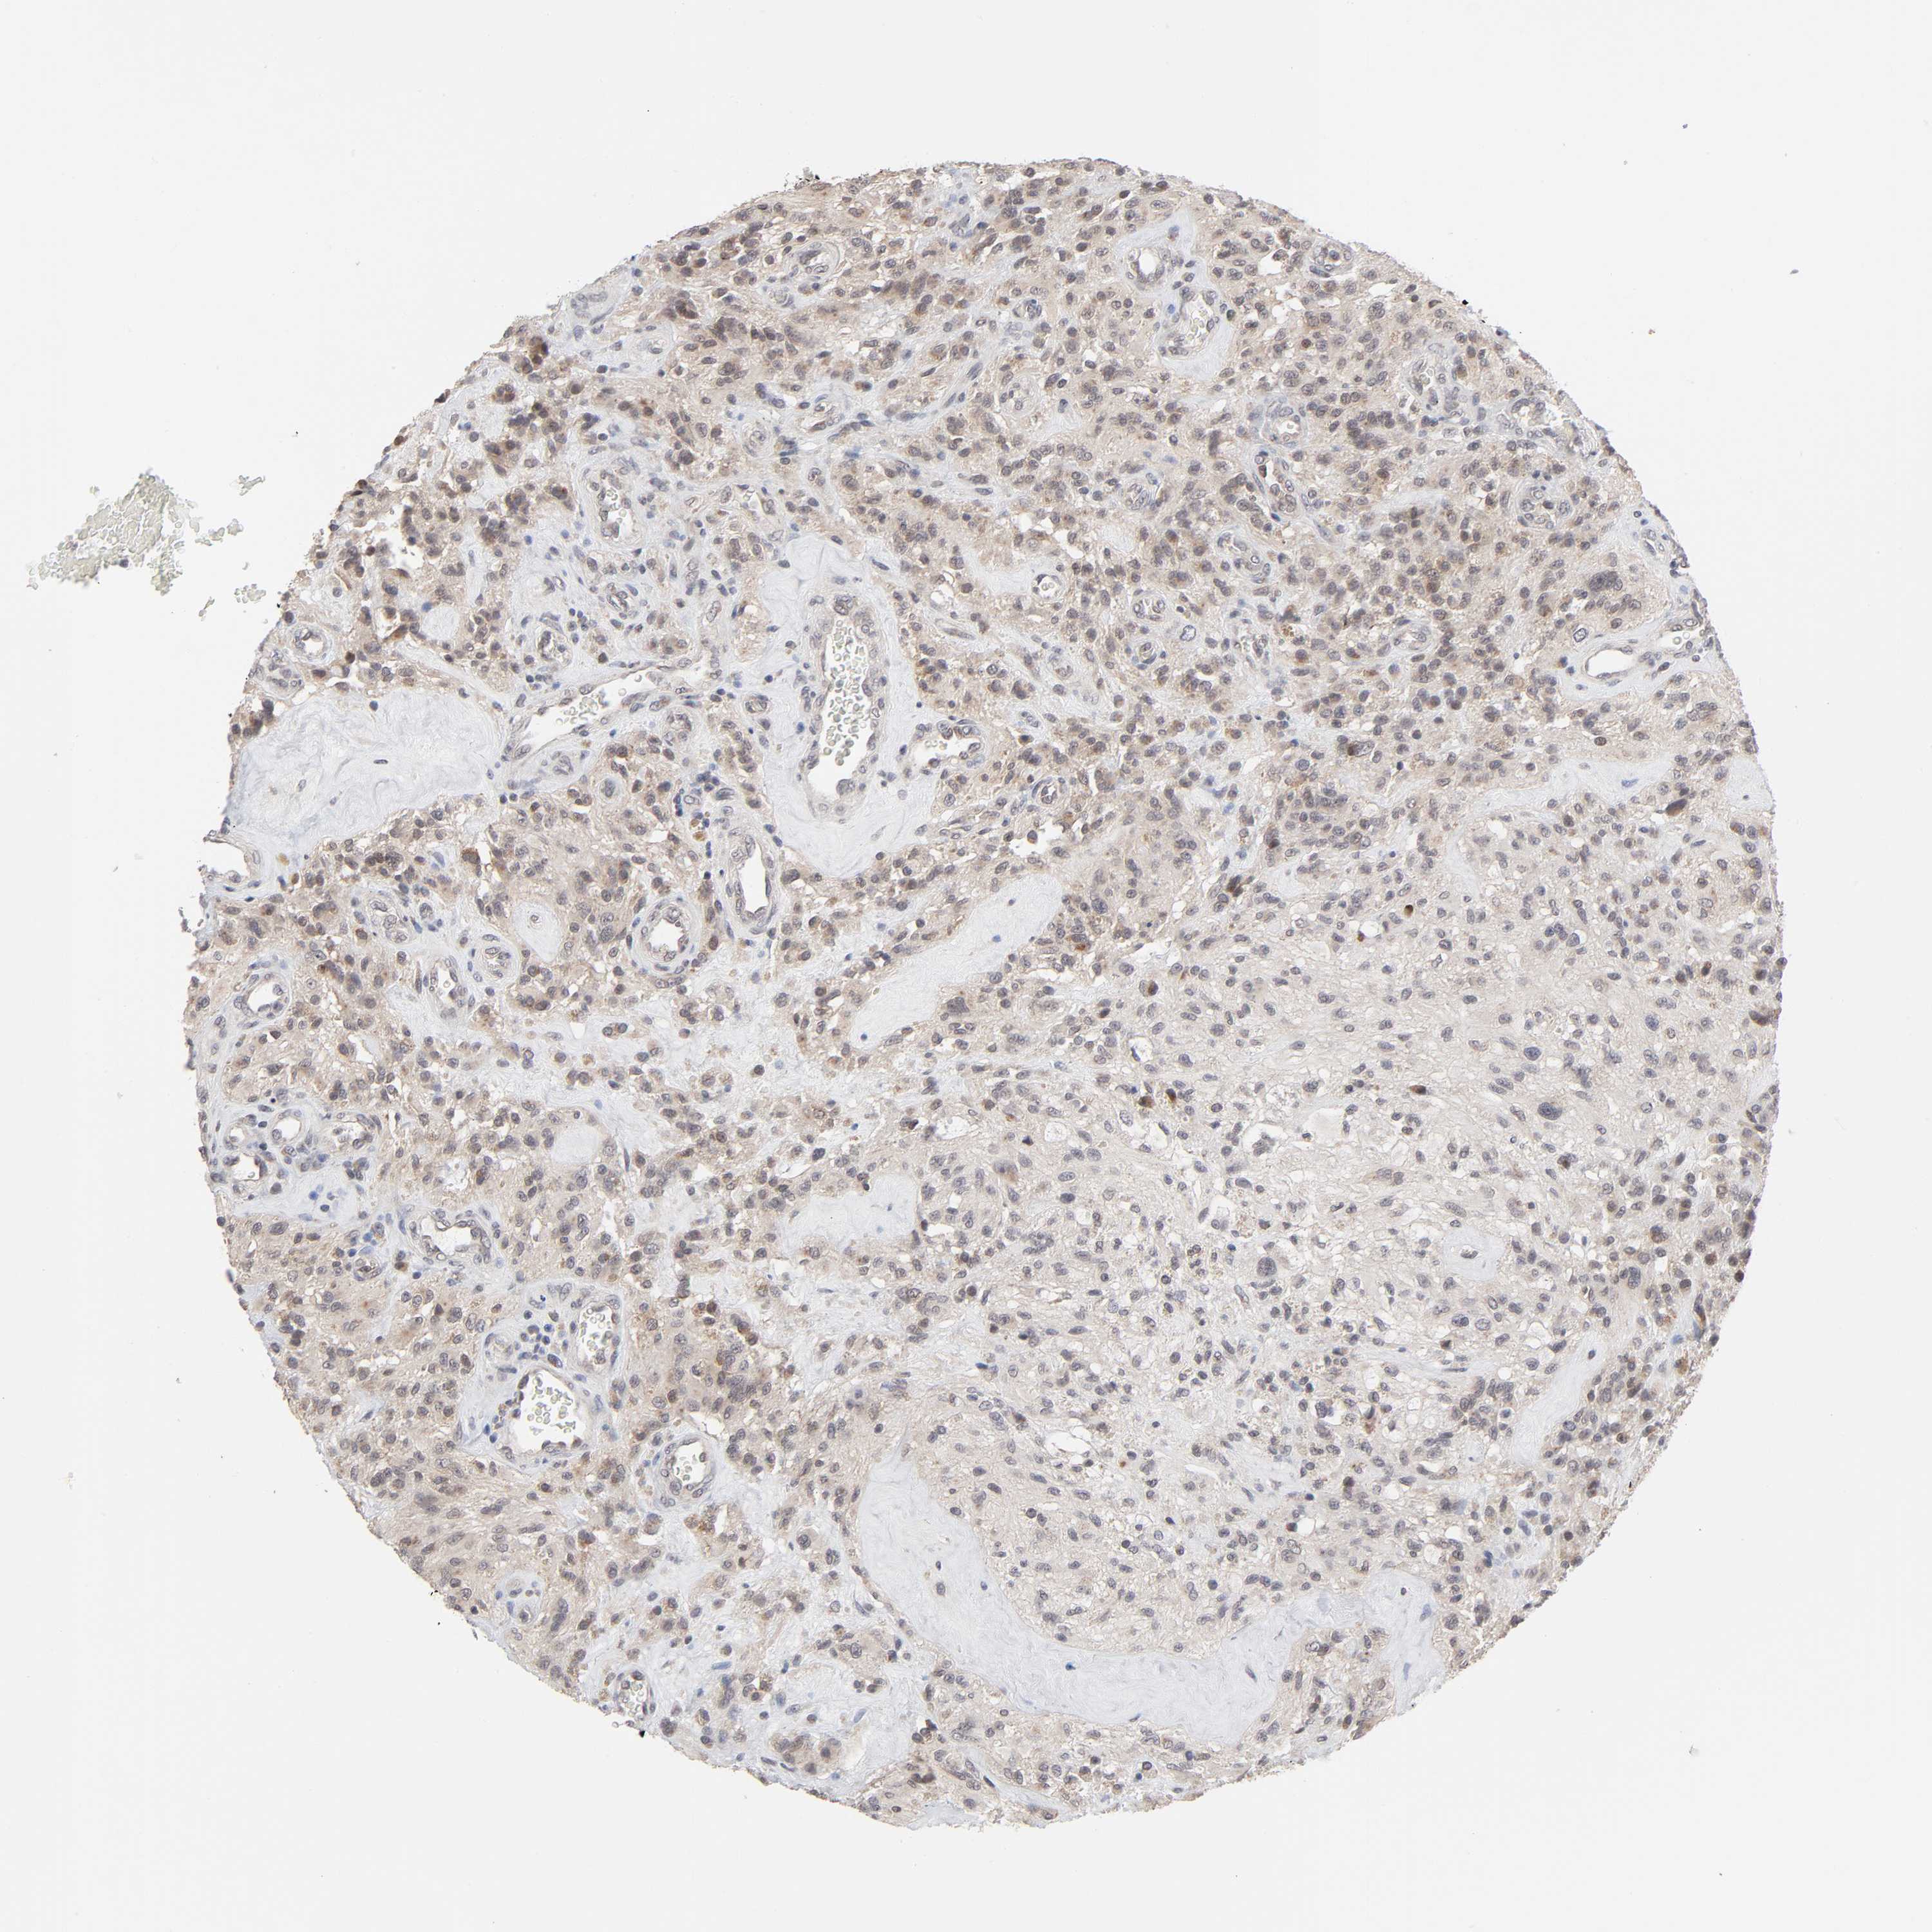

GLIOMA - Protein expressioni

A mouse-over function shows sample information and annotation data. Click on an image to view it in a full screen mode. Samples can be filtered based on level of antibody staining by selecting one or several of the following categories: high, medium, low and not detected. The assay and annotation is described here.

Note that samples used for immunohistochemistry by the Human Protein Atlas do not correspond to samples in the TCGA dataset.

Antibody stainingi

Antibody staining in the annotated cell types in the current human tissue is reported as not detected, low, medium, or high, based on conventional immunohistochemistry profiling in selected tissues. This score is based on the combination of the staining intensity and fraction of stained cells.

Each image is clickable and will lead to virtual microscopy that enables deeper exploration of all samples and also displays staining intensity scores, fraction scores and subcellular localization as well as patient and tissue information for each sample.

Antibody HPA004171

Staining

High

Medium

Low

Not detected

Intensity

Strong

Moderate

Weak

Negative

Quantity

>75%

75%-25%

<25%

None

Location

Nuclear

Cytoplasmic/membranous

Cytoplasmic/membranous,nuclear

Glioma, malignant, High grade

Glioma, malignant, NOS

Glioma, malignant, Low grade